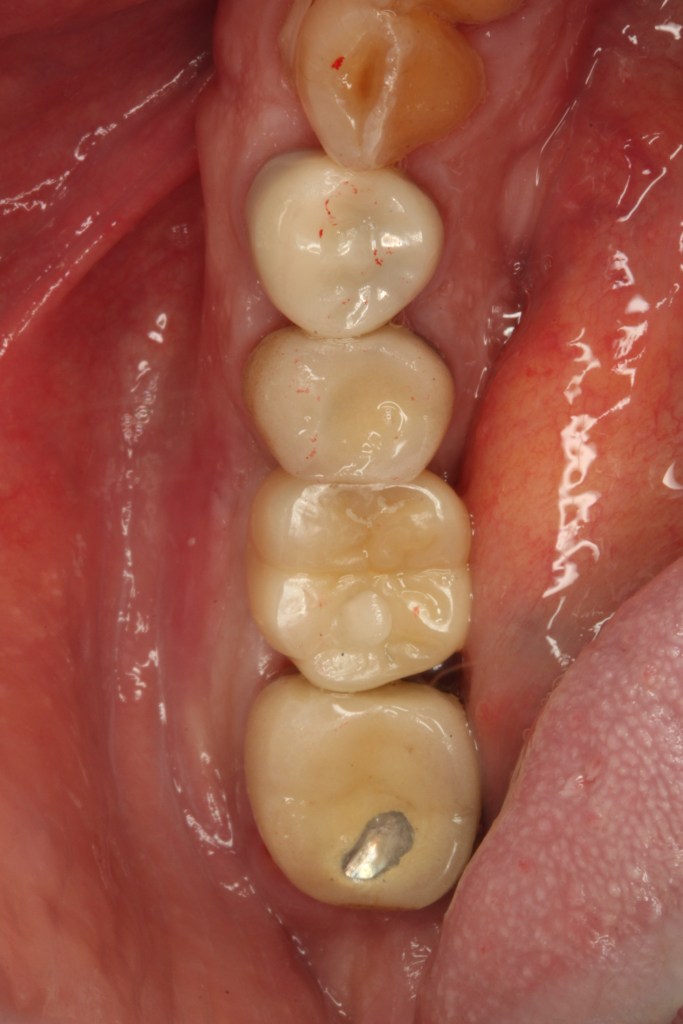

I go the dentist for final fitting of the implant that replaces the molar that was untimely ripped in London earlier this year.

Delicious and what’s more the new tooth works!